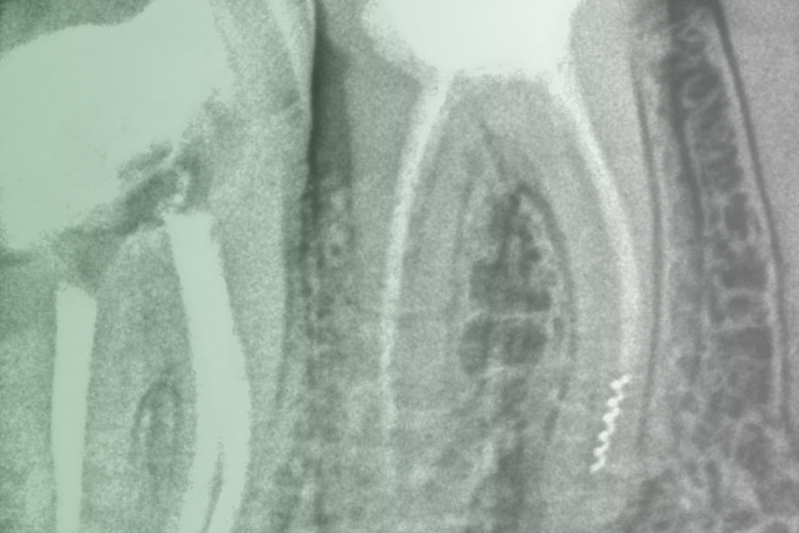

Клинический случай. Эндодонтия